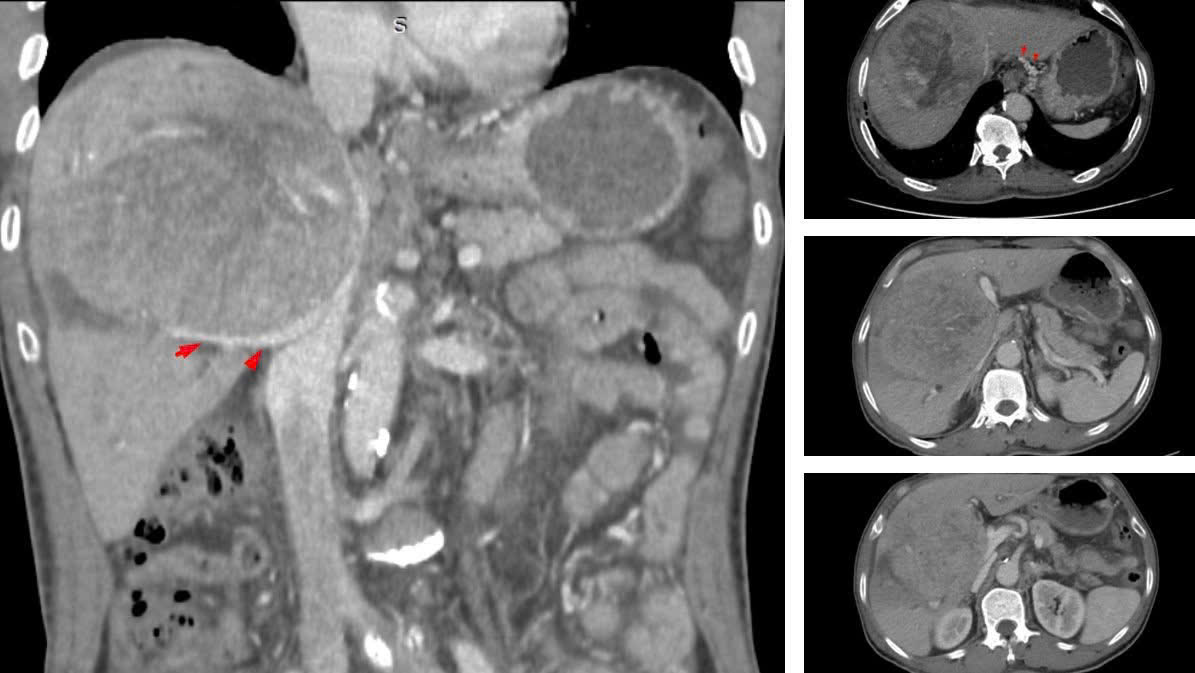

Chỉ đến khi triệu chứng rõ ràng, bệnh nhân mới đi kiểm tra, khối u gan đã phát triển với kích thước khổng lồ từ 10–12 cm. Tại một số cơ sở y tế, ông từng được tiên lượng thời gian sống không quá 9 tháng.

BSCKII Nguyễn Trường Giang, Phó Giám đốc Trung tâm Phẫu thuật Gan mật - Tiêu hóa (Bệnh viện Bệnh Nhiệt đới Trung ương) cho biết, khi nhập viện, đây là ca bệnh rất nặng. Khối u lớn chiếm gần hết nhu mô gan, chèn ép rốn gan và các mạch máu, gây cổ chướng nhẹ và phù hai chi dưới.